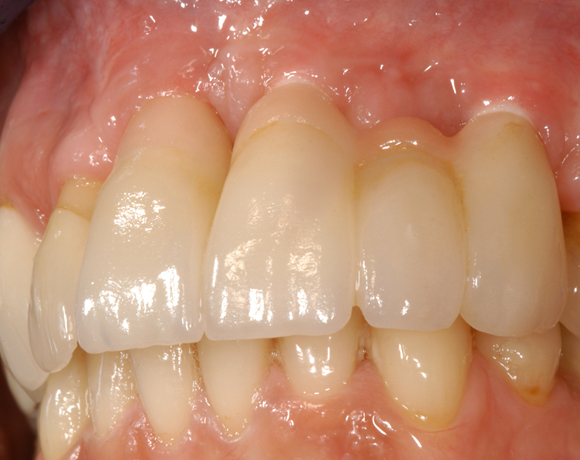

Drei Implantate in der Oberkieferfront

Das vollkeramische zweiteilige Implantat hat durch seine weiße Farbe im Frontzahnbereich keine ästhetischen Nachteile.

Ein Projekt aus dem Jahr 2011

Im vorliegenden Patientenfall mussten die 11 bis 22 aus parodontalen Gründen extrahiert werden. Die Zähne hatten Lockerungsgrad III, und es bestand ein starker horizontaler Knochenabbau. Das Ergebnis zeigt die Abschlusssituation nach Knochenaufbau und der Insertion von drei Vollkeramikimplantaten.